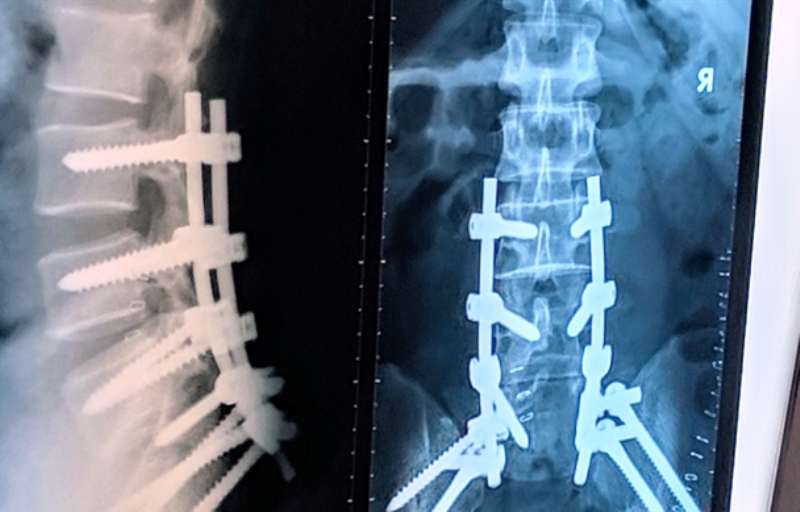

Ảnh chụp X-quang, cột sống bệnh nhân được hỗ trợ bằng dụng cụ nâng đỡ cột sống. Ảnh: Phan Nhơn

Bệnh nhân T. tiếp tục lên bàn mổ lần 3, ê-kíp lần này sẽ căt bỏ khối u xương, cắt bỏ xương cùng cụt và đặt dụng cụ để nâng đỡ cột sống cho người đàn ông.

Ca mổ kéo dài từ 8 giờ sáng đến 15 giờ chiều. Ca mổ vô cùng phức tạp, bác sĩ Hiển từng khuyên bệnh nhân cân nhắc vì nhiều biến chứng có thể xảy ra do khối u ở vị trí nhiều cơ quan qua lại như: trực tràng, ruột, mạch máu, bàng quang… Song, ê-kíp muốn lấy trọn khối u để tránh tái phát, giúp bệnh nhân có thể đi lại bình thường.